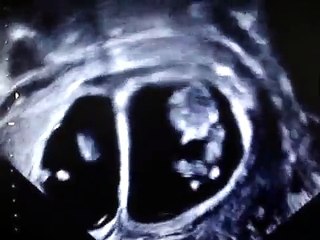

What to Expect at Week 20 | Week by Week Pregnancy Guidebr br The video is presenting What to Expect at Week 20 valuable information but also try to cover the following subject:br -20 week ultrasoundbr -anatomy scan 20 weeks what to expectbr -week twenty of pregnancybr br So you want to find out more about What to Expect at Week 20, I did too and here's the video that I created around this topic.br What to Expect at Week 20 intrigued me so I did some research study and published this to YouTube .